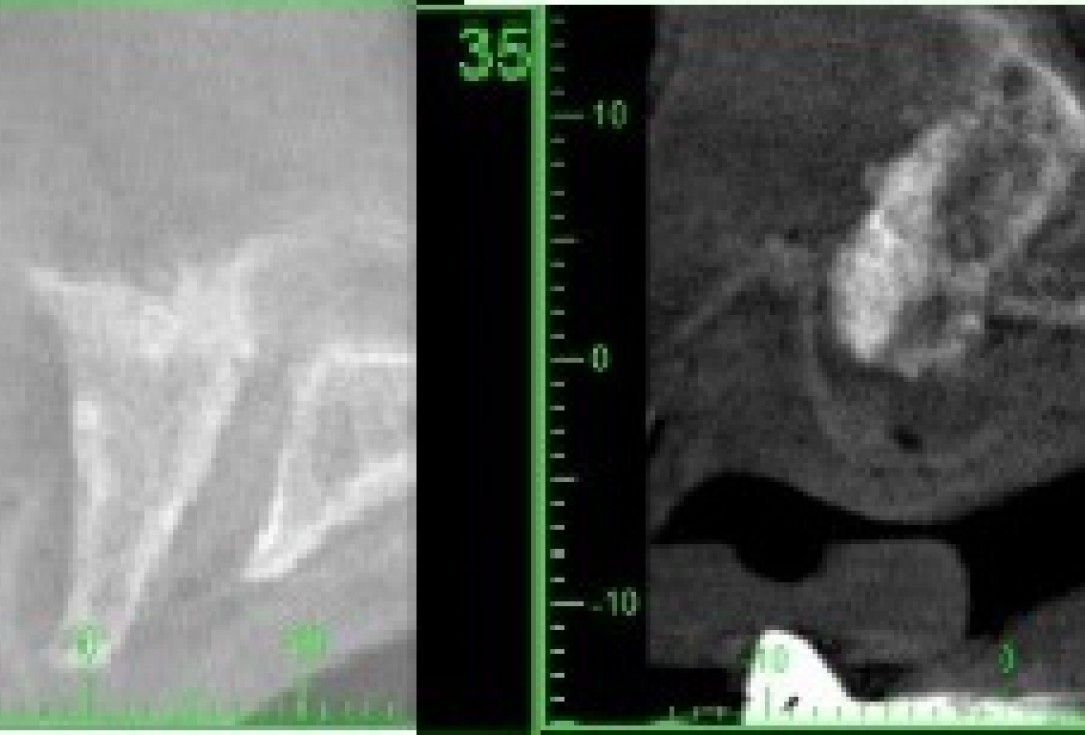

3/21 - CT scan pre-op: Thin maxillary ridge

17/21 - CT scan 6 months post-op: Stable bone with Ø 8mm width

21/21 - Before and after CT scan: approx. 3 mm bone gain